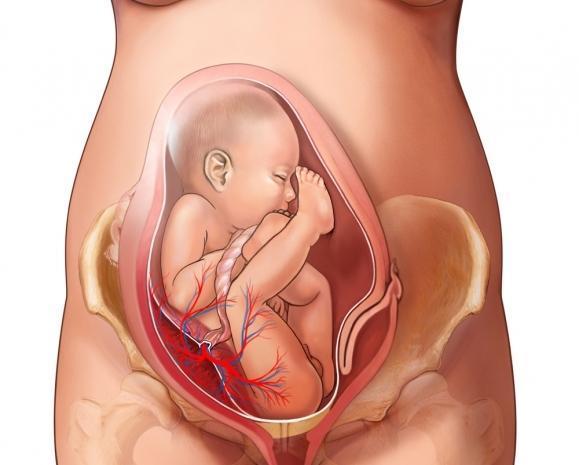

4/21![İki kez hamile kaldım, kese oluştu ama bebek gelişmedi İki kez hamile kaldım, kese oluştu ama bebek gelişmedi]()

İki kez hamile kaldım, kese oluştu ama bebek gelişmedi